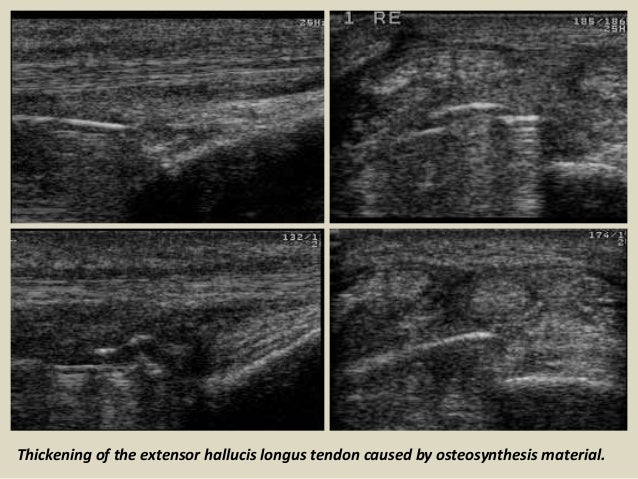

Thickening of the extensor hallucis longus tendon caused by osteosynthesis material.

41. 41. Thickening of the extensor hallucis longus tendon caused by osteosynthesis material.